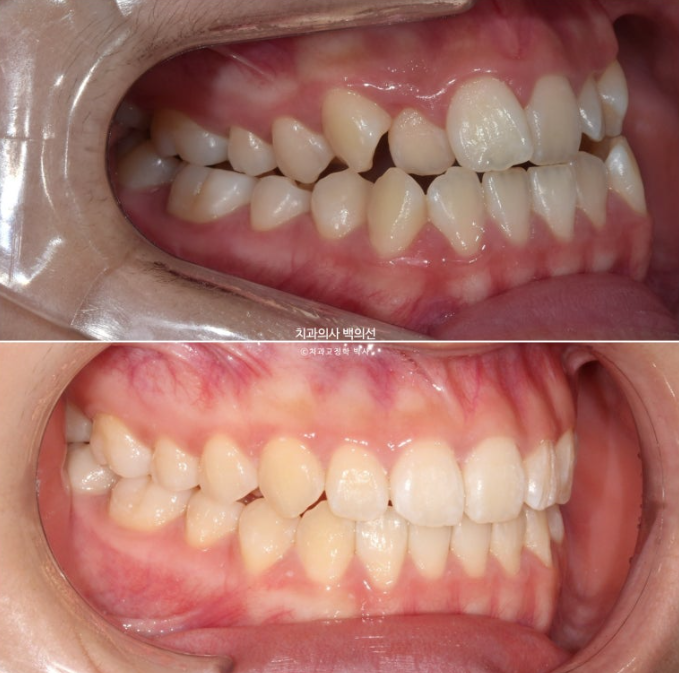

23.10

앞니에 개방교합이 보이고 앞니뿐 아니라 어금니까지 반대교합이 보입니다.

사진처럼 양쪽 어금니가 모두 거꾸로 물릴 정도로 위턱이 좁다면 악궁확장장치를 먼저 따로 써야 합니다.